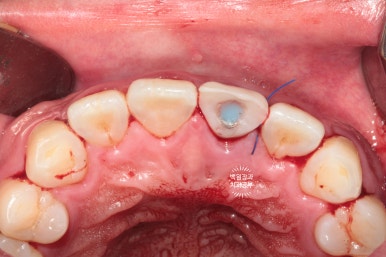

입천장 쪽에서 바라보았을 때, 이미 잇몸라인보다 깊은곳까지 부러져 있는 뿌리만 남은 치아를 보실 수 있어요.

예전에 신경치료를 해놓은 치아라 앞니 뿌리가 이미 검게 변해버린 상태입니다.

뒷 부분을 하늘색 임시재료로 메꿔드렸고,

환자분은 왼쪽 상태로 귀가하실 수 있었습니다.